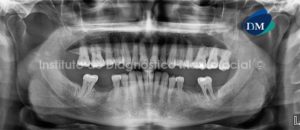

Paciente masculino, 11 años de edad es referido al Instituto de Diagnostico Maxilofacial (IDM) para evaluación general.A la evaluación de la radiografía panorámica (ortopantomografía) se